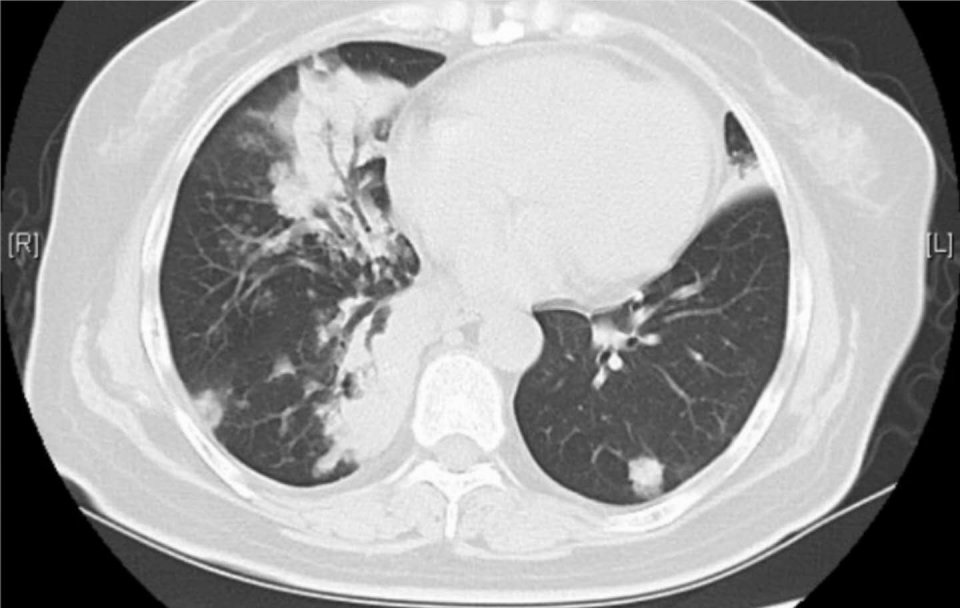

4.女性52岁,双肺粘液性腺癌(合并了气道播散),做过6次化疗和2种靶向药物治疗,生存五年多:

这是首都北京的一位病人,当初在军总医院进修学习时候遇到的,最后一次复查,控制得还不错: